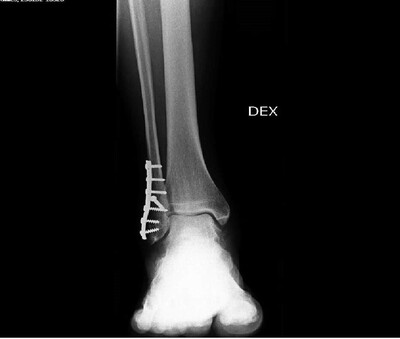

Перелом лодыжки со смещением

Год начался с перелома лодыжки.

Будет операция, пока на костном вытяжении.